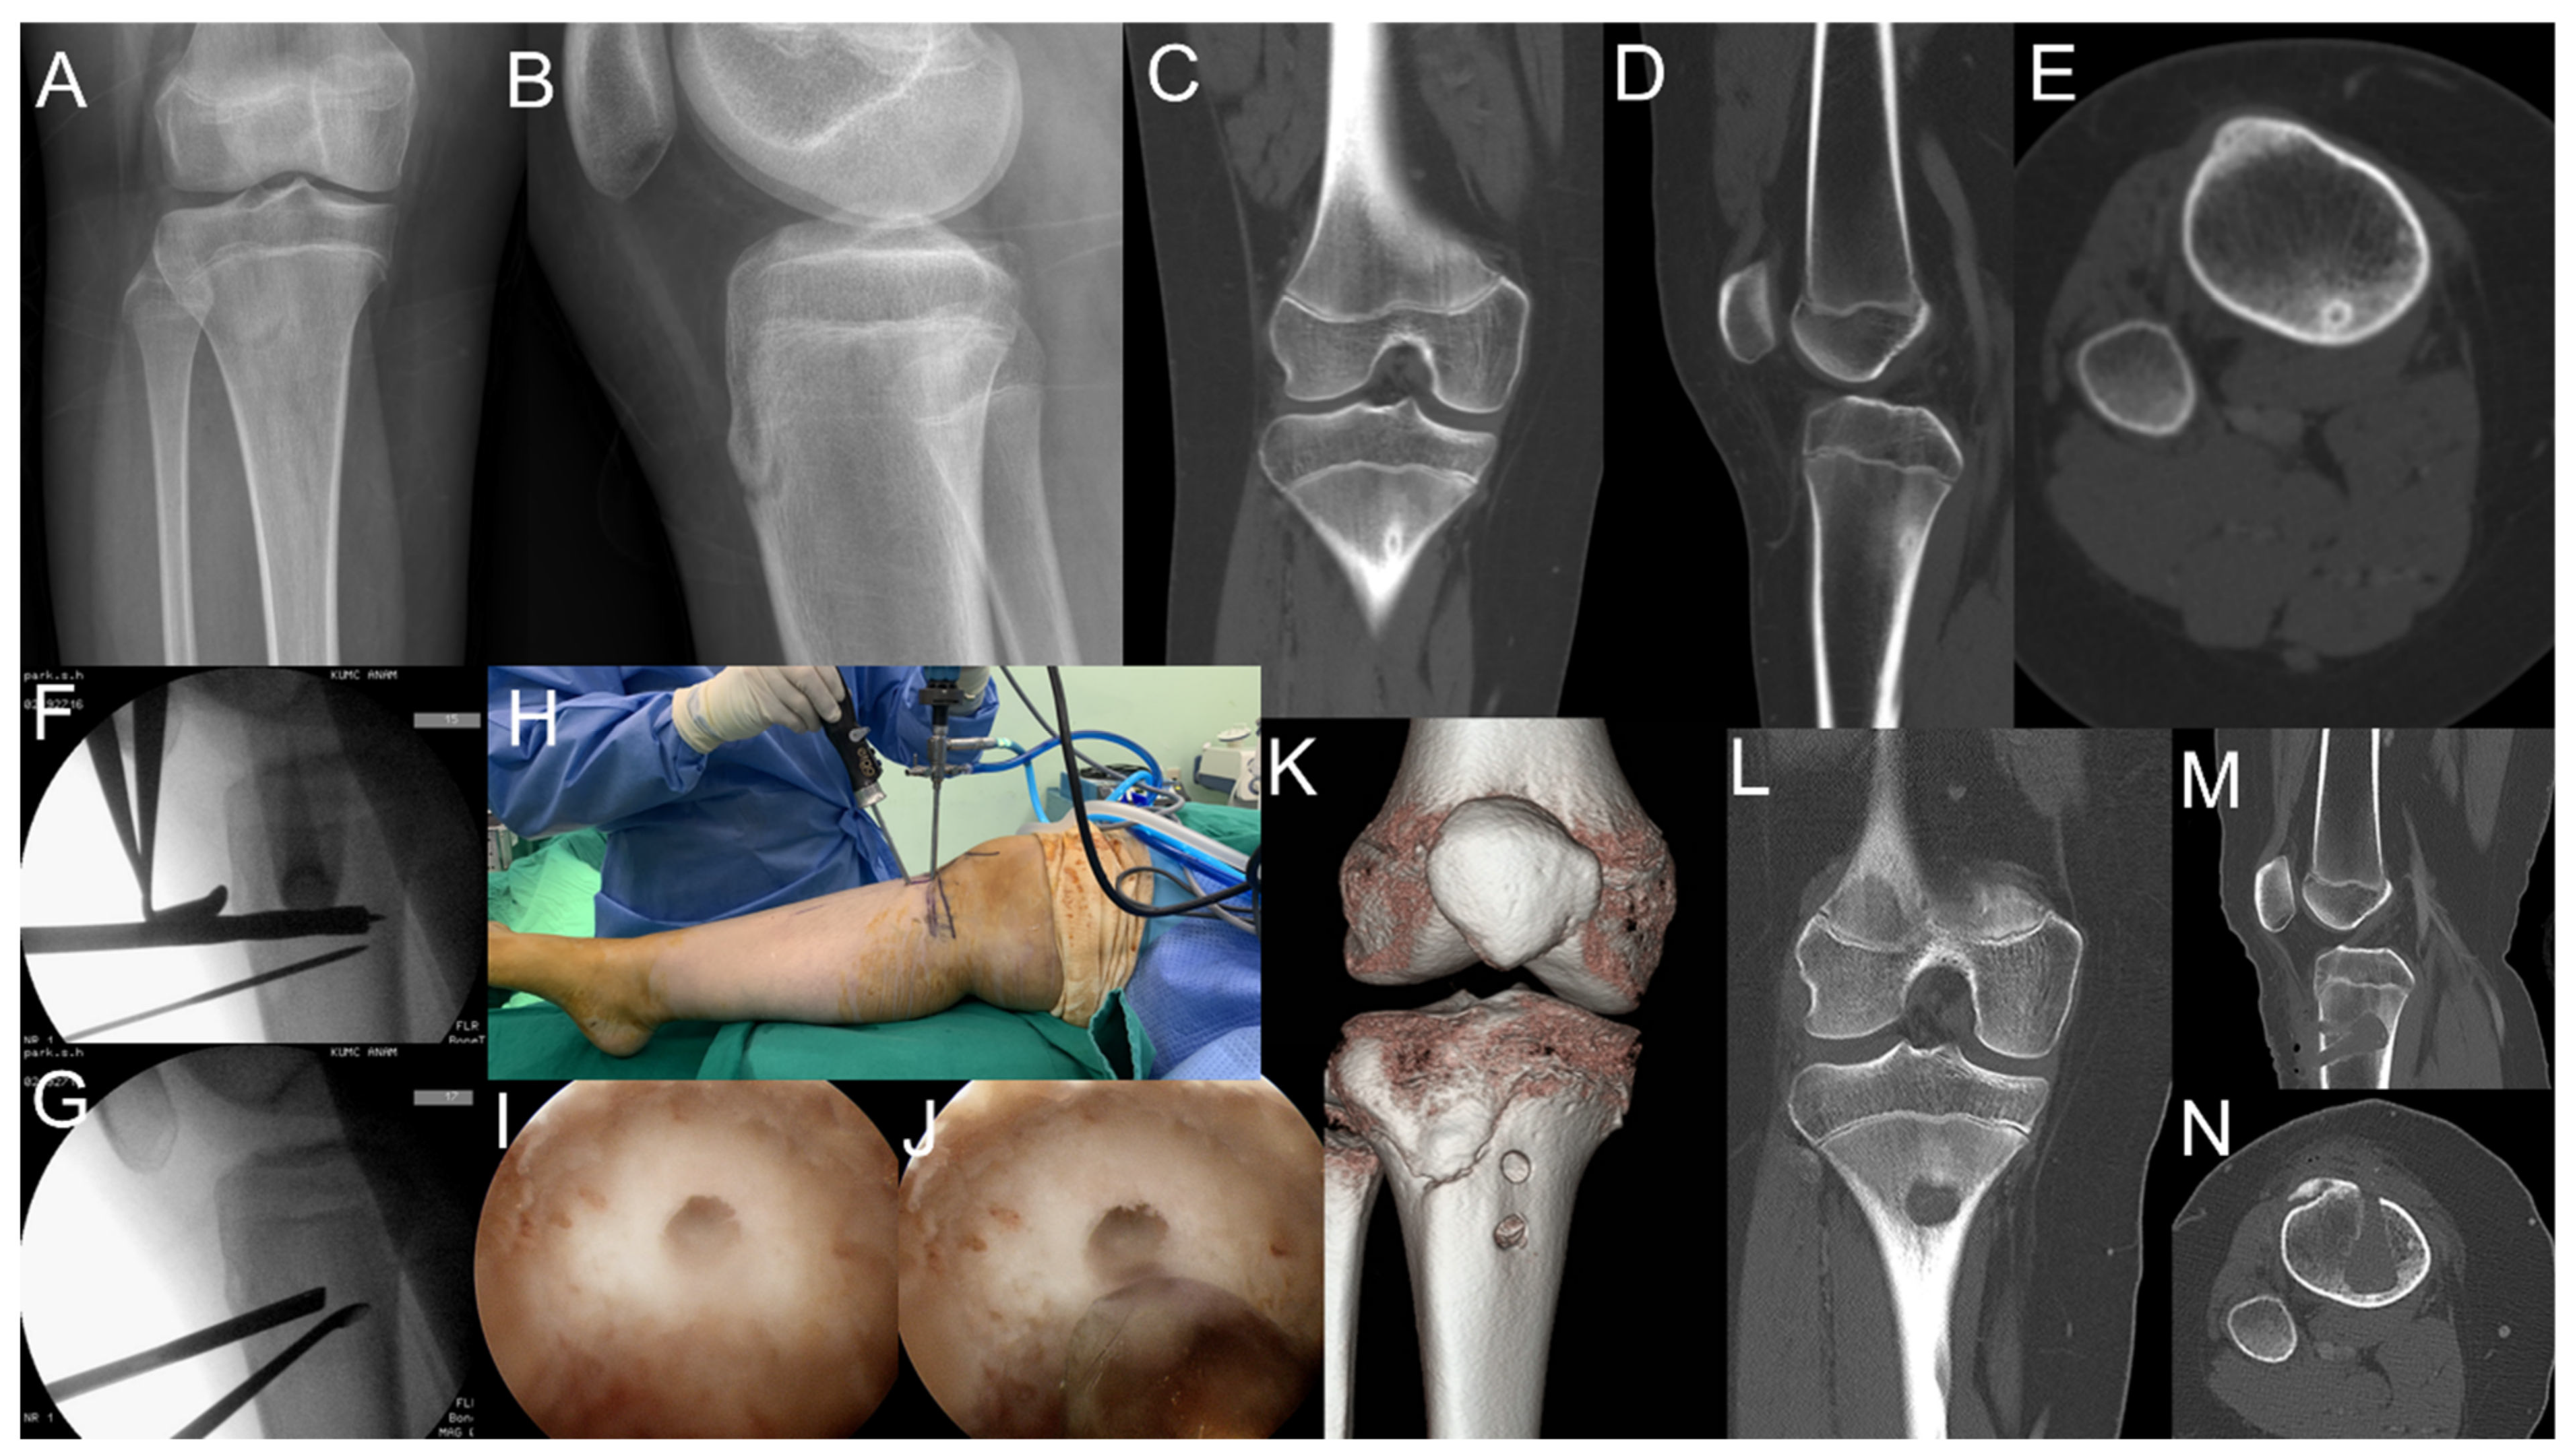

2.2. Case 2